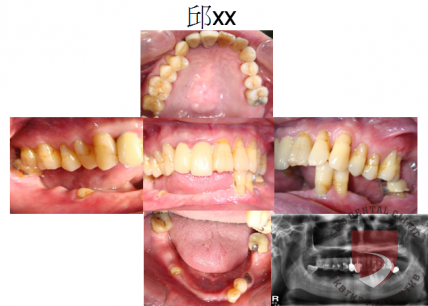

全口重建邱xx

成效因人而異,須遵從專業醫師指引